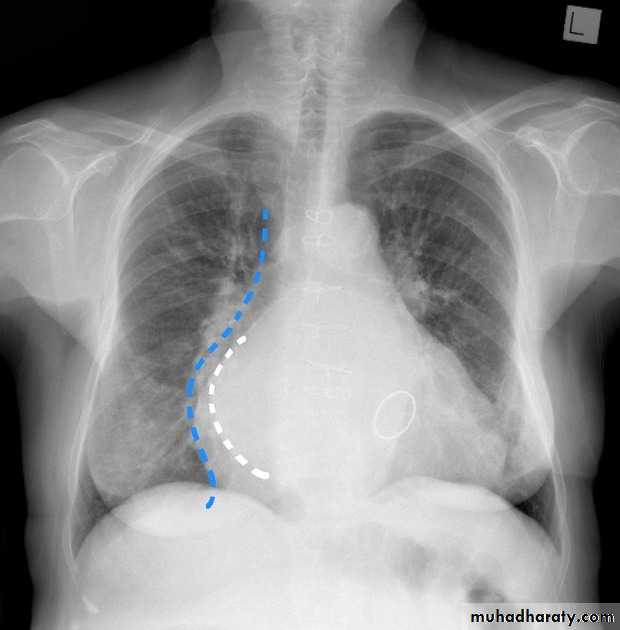

boot shape (wooden boot) heart (TOF)

CXR of a child, PA view shows:"boot shaped" heart with an upturned cardiac apex due to right ventricular hypertrophy and concave pulmonary arterial segment .

Pulmonary oligaemia due to decreased pulmonary arterial flow.